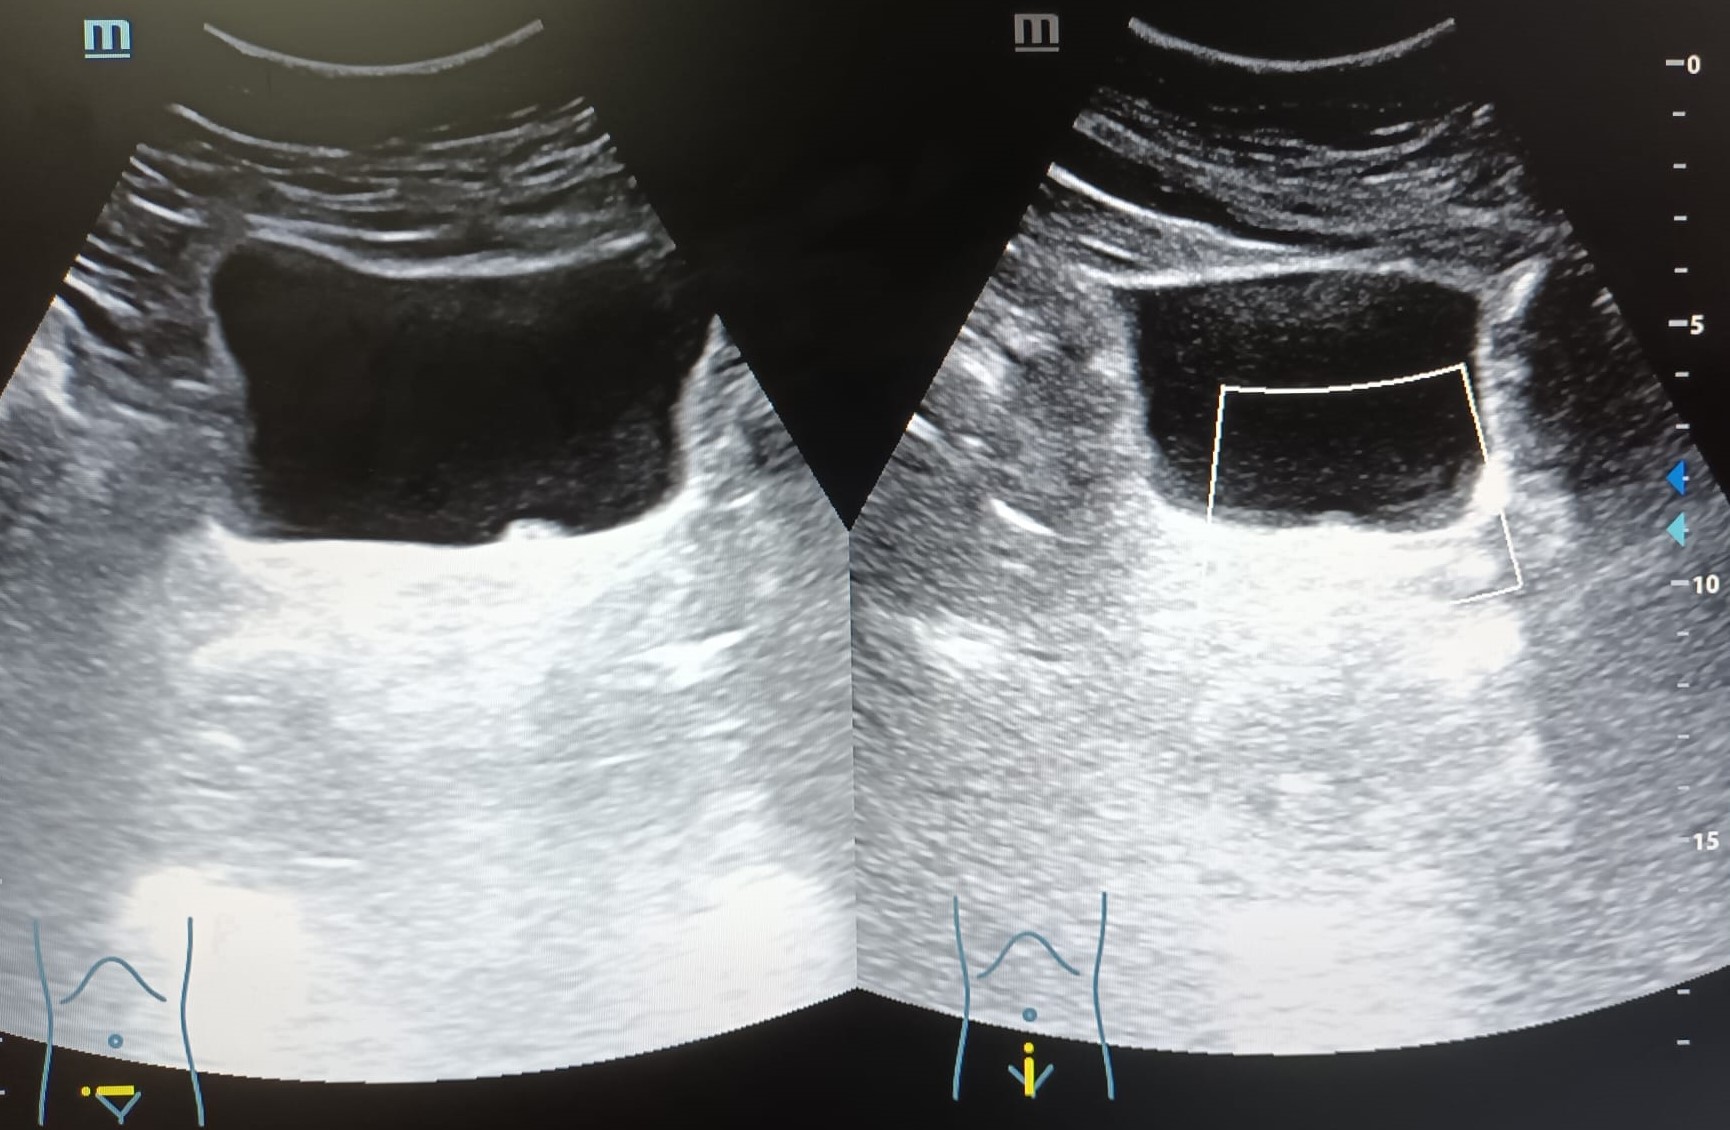

Vejiga: lesión hiperecogénica, de bordes bien definidos, adherida a pared, en zona del trígono vesical, colindante con uréter izquierdo, que no capta Doppler, de aproximadamente 4,2 x 6,7 mm.

Ante el hallazgo ecográfico de una lesión vesical es necesario hacer diagnóstico diferencial entre distintas entidades como pueden ser neoplasias vesicales, ureterocele, litiasis, coágulos, etc.

El Servicio de Urología confirma que se trata de una neoplasia vesical.